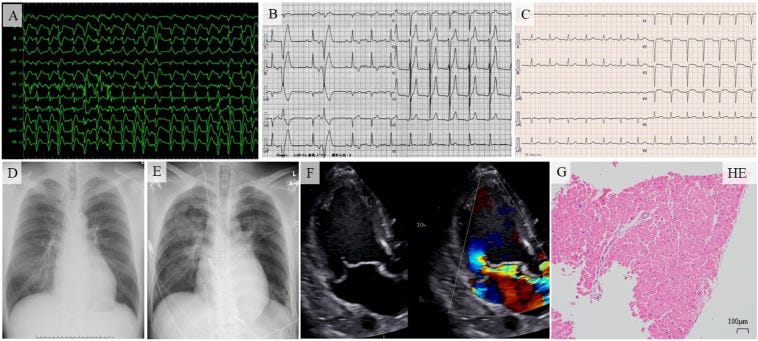

Dec 2022 - 27-year-old man suffers rare fatal fulminant myocarditis 8 days after mRNA COVID-19 vaccination. Autopsy reveals significant mixed inflammatory infiltration. Steroid therapy could be effective in such cases. https://pubmed.ncbi.nlm.nih.gov/35812802

Oct 2022 - 61-year-old woman with no significant medical history experienced fatal fulminant myocarditis after SARS-CoV-2 vaccination; autopsy shows severe myocarditis with extensive myocytolysis, highlights need to study immune reactions post-vaccination. https://pubmed.ncbi.nlm.nih.gov/36040128